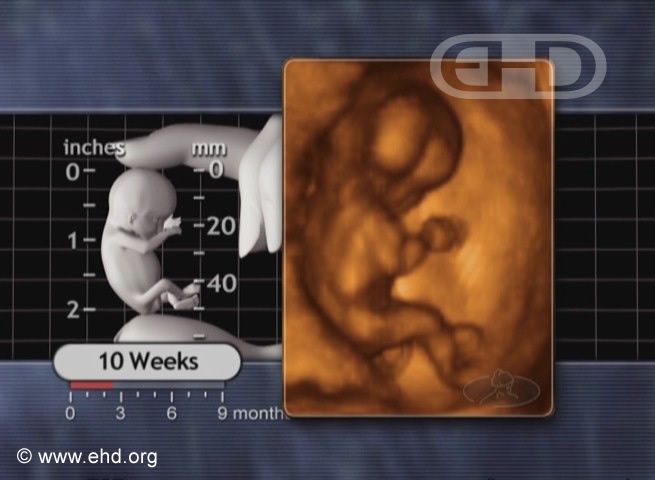

The 10-Week Fetus

10 weeks

From The Biology of Prenatal Development.Buy Now

When exercising, don't forget to include the arms and legs! This little one has the right idea. Watch the movie and maybe you will be inspired to exercise too!

Label Key:

1. head

2. right thigh

3. right hand

4. knee

5. lower leg

All ages referenced to fertilization, not last menstrual period.